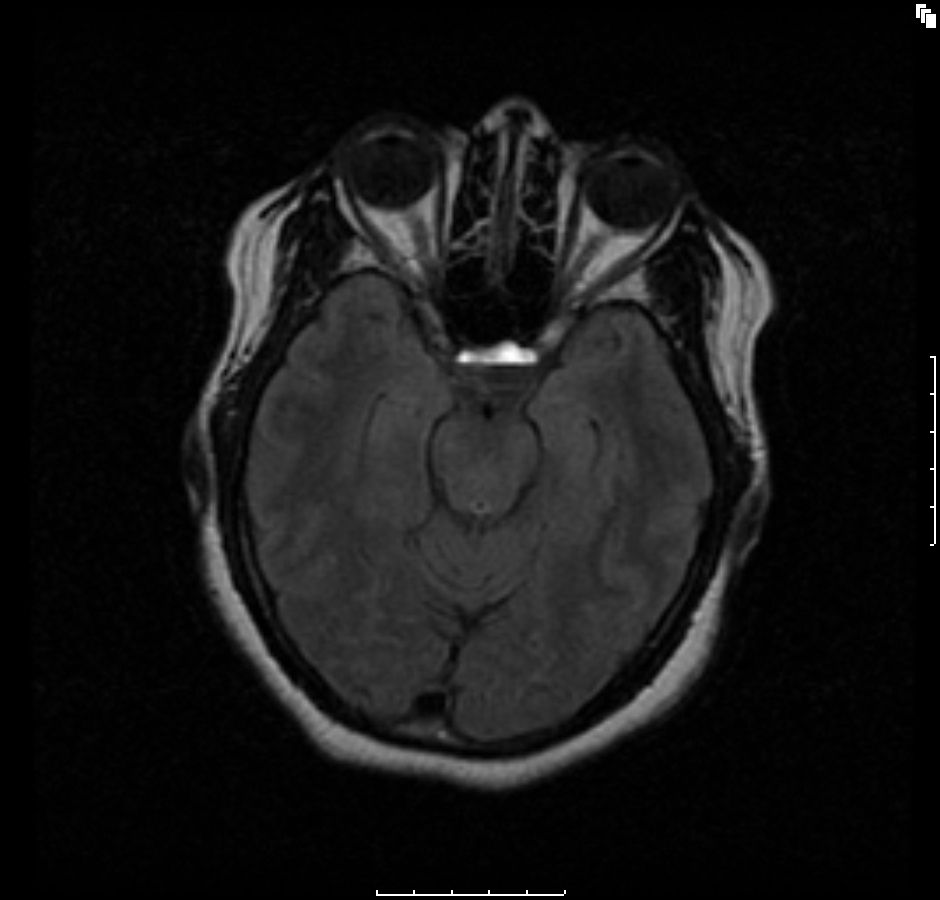

Figure A3: Axial flair T2-weighted 3 planar image showing a hypointense bottom layer and a hyperintense upper layer (green arrow) consistent with hemorrhagic pituitary macroadenoma.

The initial brain scans were obtained 6 months after her initial diagnosis (3 months into her pregnancy) and revealed a hemorrhagic pituitary macroadenoma (Figures A1-4). The patient recollects that a week before the scan, she suffered an episode of severe headache with visual disturbance of the right eye. She did not seek medical attention at the time but did keep an appointment for the brain imaging the following week. At the time of the imaging, she reported that her symptoms had fully resolved.